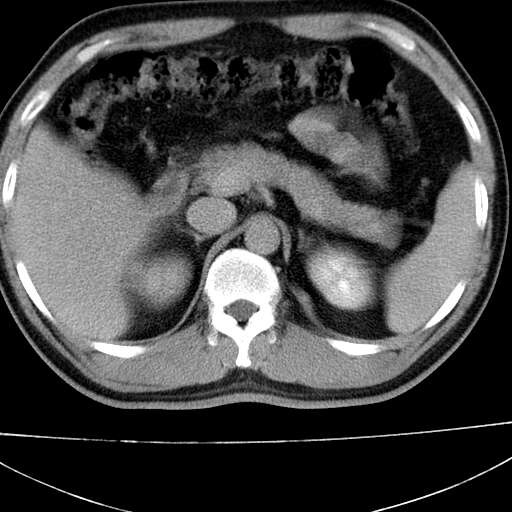

标题: CT21921:腹膜后腔肿物。患者男39Y。体检。增强扫描时间欠准 [打印本页]

标题: CT21921:腹膜后腔肿物。患者男39Y。体检。增强扫描时间欠准

2、左下膈肌脚外缘结节状病变,与胸膜交界面呈锐角,胸膜下脂肪线可见,定位于肺内,考虑支气管囊肿或肺隔离征可能性大。

1)考虑左肺下叶后基底段(或左下胸后壁胸膜)软组织团块,性质待定;建议行进一步检查。2)左肾结石。

左膈肌连续性中断,左侧膈疝可能性大.

左膈肌角后腹膜腔见肿物影,其内见脂肪密度灶及软组织密度灶,强化不明显。病灶大部在后腹膜内。考虑异位嗜铬细胞瘤或脂肪肉瘤、畸胎瘤

1)考虑左肺下叶后基底段软组织团块,性质待定;建议行进一步检查。2)左肾结石。

左膈肌连续性中断,左侧膈疝可能性大

左下肺隔离症,可见从胸主动脉发出异常血管供应